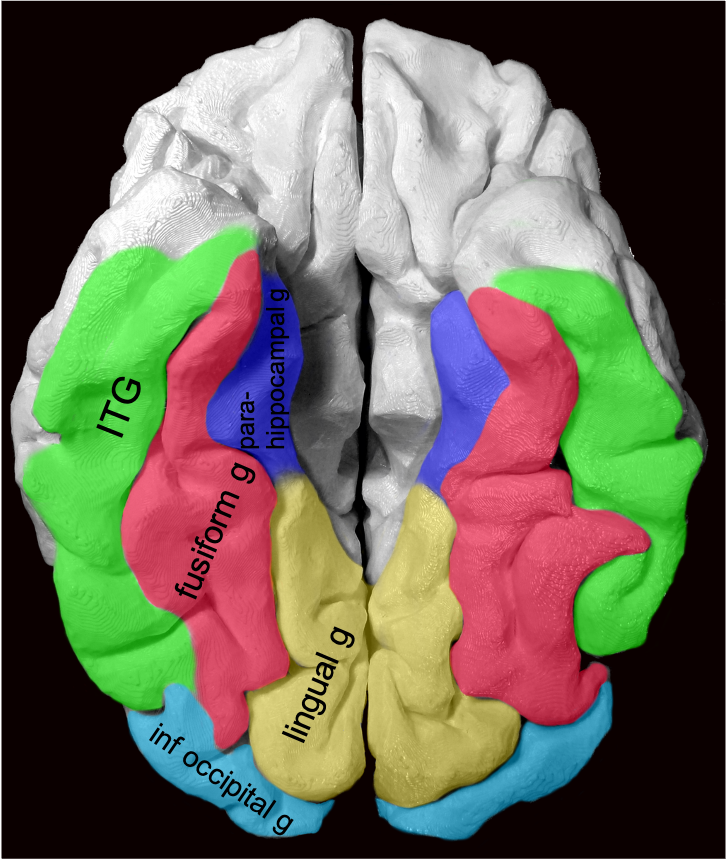

This location can be a bit difficult to describe if you aren’t up on gyral anatomy. Is it med temporal lobe? occipital lobe? limbic? Describing gyral location is more precise, can explain expected symptoms, and clue in future surgical approach.

Gyral anatomy of inf occipitotemporal surface: The inf. temp. gyrus wraps from lateral https://abs.twimg.com/emoji/v2/... draggable="false" alt="➡️" title="Pfeil nach rechts" aria-label="Emoji: Pfeil nach rechts">inferior. The fusiform and lingual gyri span from occipital lobe posteriorly to temporal lobe anteriorly. Parahippocampal is medial temporal (anterior continuation of the lingual g).

https://abs.twimg.com/emoji/v2/... draggable="false" alt="➡️" title="Pfeil nach rechts" aria-label="Emoji: Pfeil nach rechts">inferior. The fusiform and lingual gyri span from occipital lobe posteriorly to temporal lobe anteriorly. Parahippocampal is medial temporal (anterior continuation of the lingual g).

The lingual gyrus is involved in holistic visual and word processing, encoding visual memories, imagery, and dreaming. The ganglioglioma in the shown case is centered in the lingual gyrus.

Fusiform g is just lateral to lingual g on the inf surface of temporal lobe, separated by collateral sulcus. It& #39;s medial to the ITG, separated by ITS. Involved in face and body recognition; word form recognition (on left). (Fusiform g was not definitively involved by tumor). 9/13

Parahippocampal g. is anterior continuation of lingual g. Part of Limbic System. Important in memory encoding and retrieval, visual and social contextualizing.

inferior. The fusiform and lingual gyri span from occipital lobe posteriorly to temporal lobe anteriorly. Parahippocampal is medial temporal (anterior continuation of the lingual g).6/13" title="Gyral anatomy of inf occipitotemporal surface: The inf. temp. gyrus wraps from lateralhttps://abs.twimg.com/emoji/v2/... draggable="false" alt="➡️" title="Pfeil nach rechts" aria-label="Emoji: Pfeil nach rechts">inferior. The fusiform and lingual gyri span from occipital lobe posteriorly to temporal lobe anteriorly. Parahippocampal is medial temporal (anterior continuation of the lingual g).6/13" class="img-responsive" style="max-width:100%;"/>

inferior. The fusiform and lingual gyri span from occipital lobe posteriorly to temporal lobe anteriorly. Parahippocampal is medial temporal (anterior continuation of the lingual g).6/13" title="Gyral anatomy of inf occipitotemporal surface: The inf. temp. gyrus wraps from lateralhttps://abs.twimg.com/emoji/v2/... draggable="false" alt="➡️" title="Pfeil nach rechts" aria-label="Emoji: Pfeil nach rechts">inferior. The fusiform and lingual gyri span from occipital lobe posteriorly to temporal lobe anteriorly. Parahippocampal is medial temporal (anterior continuation of the lingual g).6/13" class="img-responsive" style="max-width:100%;"/>